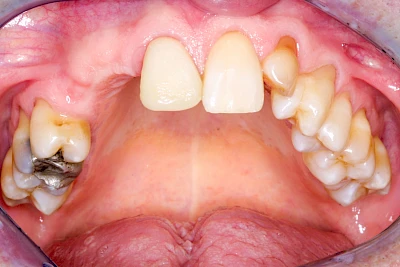

Implantate: Kronen & Brücken

Fehlen einzelne Zähne und die Nachbarzähne sind unbeschadet oder gut zahnärztlich versorgt, werden immer häufiger Implantate gewählt, um die Lücken zu schließen. Auch bei größeren oder verteilten Lücken, wenn keine herausnehmbare Prothese gewünscht ist, werden Implantate für Kronen- bzw. Brückenversorgungen gesetzt. In Einzelfällen entscheiden sich sogar zahnlose Patienten für eine festsitzende Versorgung auf Implantaten.

Varianten zur Verankerung von festsitzendem Zahnersatz auf Implantaten